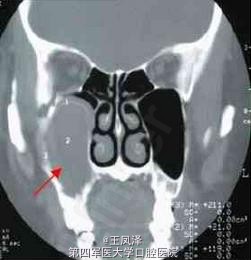

患者女性,38 岁。主诉:发现右面颊部肿物一个半月。查体:右颧弓下方2.5cm×3cm 肿物,囊性感,与周围组织无粘连。CT 鼻窦冠扫示:右上颌骨囊肿向内突入右上颌窦(齿槽骨缺损),向外突向颌骨外的软组织中。术后病理:右上颌骨囊肿,部分囊壁可见慢性炎细胞浸润。